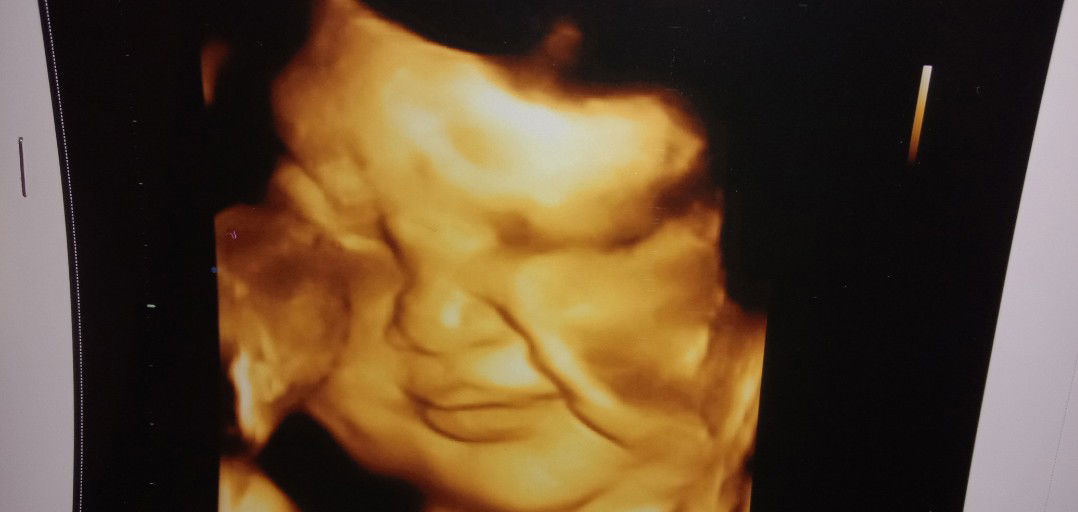

39w5d masih betah didalem

Minta saran dong biar cepet launcing tanpa perut di edel edel bun ?☺ Udah konsul udah googling , bahkan udh dikutin semuanyaa , Tapii yg didalem msh betah ajanihh??